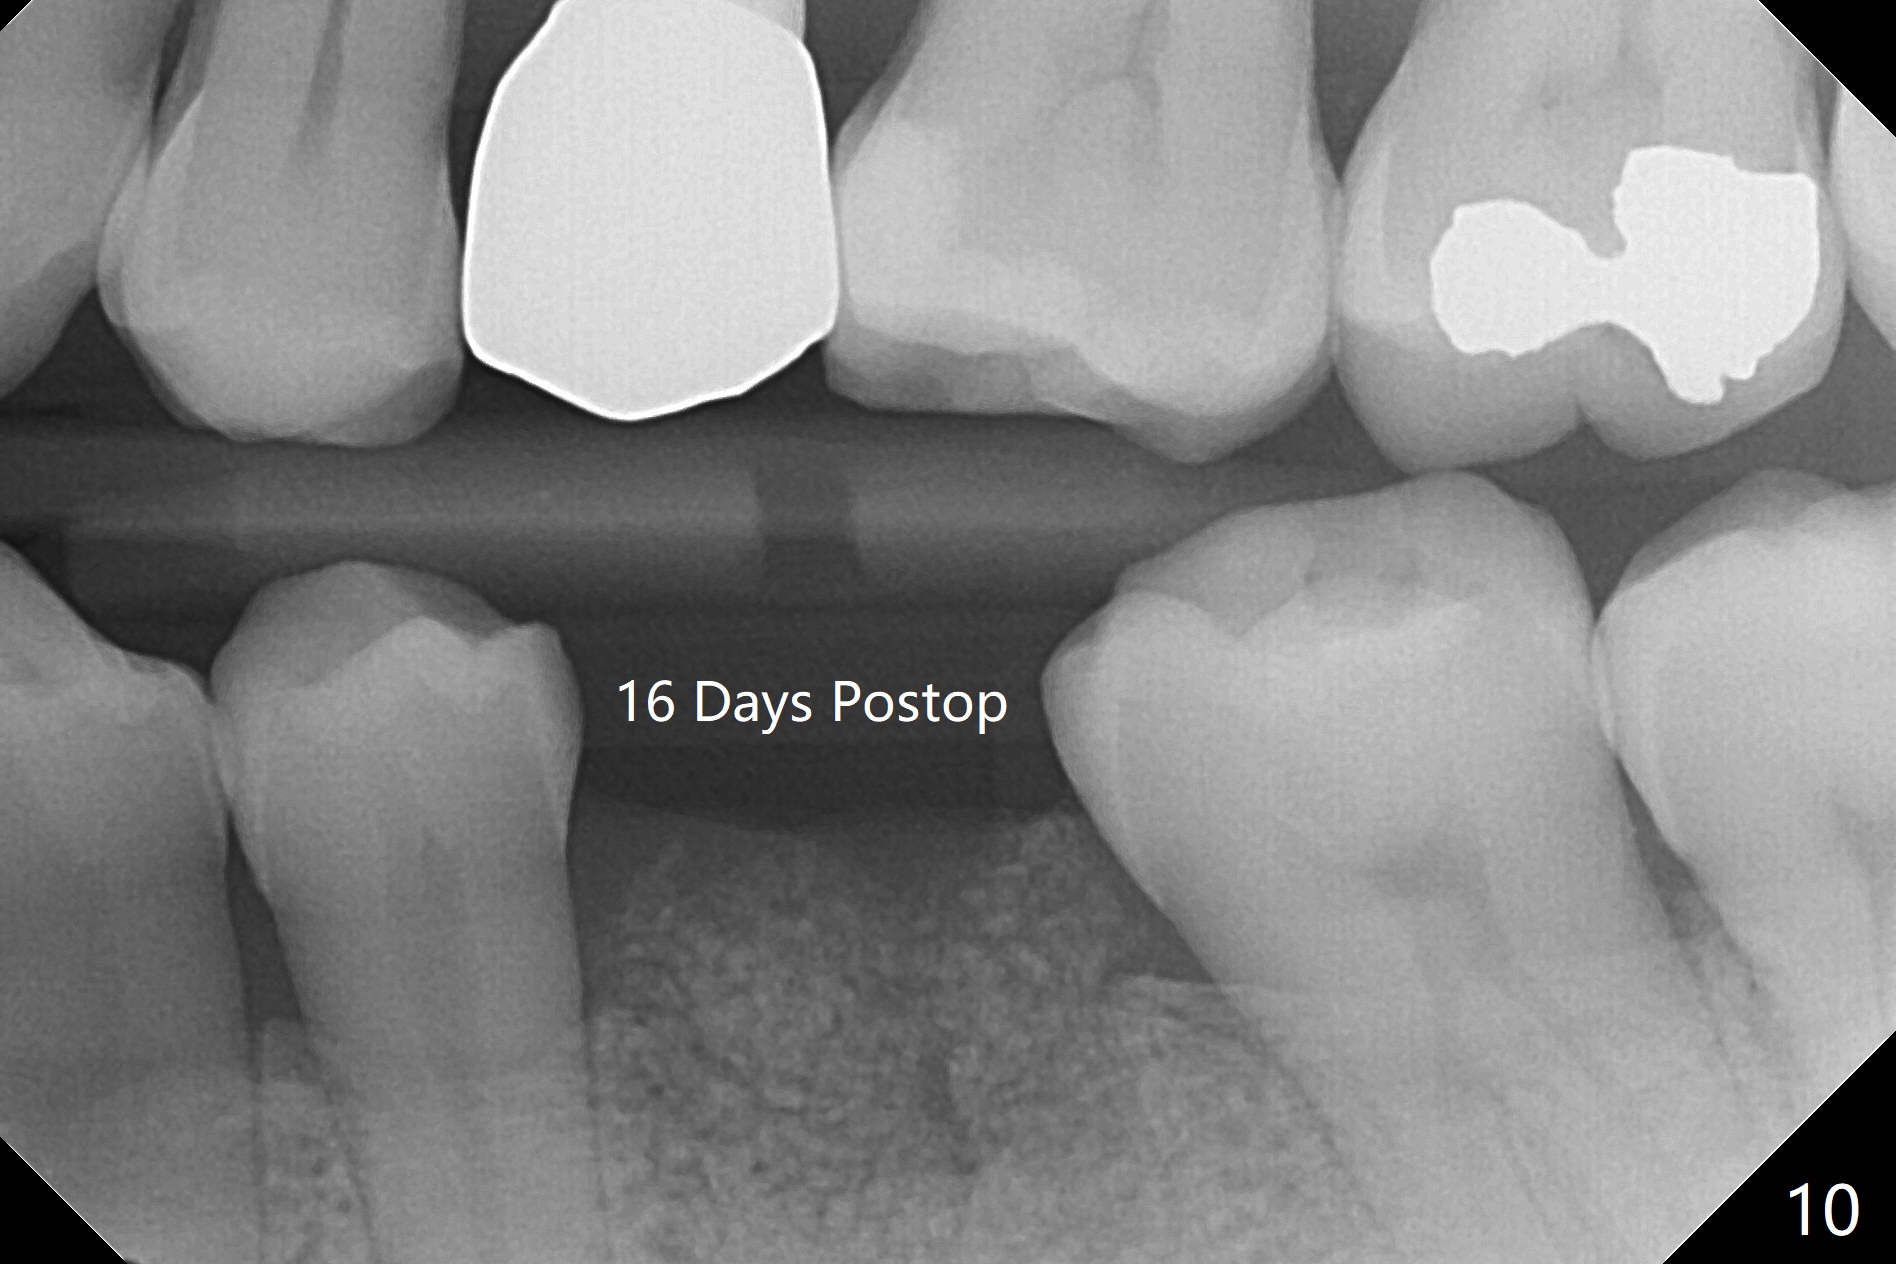

When the patient returns for #15 comp, the bone resorption and swelling at #19 are worse than those 3 years ago (Fig.1,2). After debridement, the mesial socket is large, while the septum is thin, irregular and with undercut (Fig.3). It seems difficult to obtain primary stability for an immediate implant. Vanilla bone and cortical bone hydrated with GEM21 S are placed for socket preservation (Fig.4,5), followed by 12x12 mm BioXclude and 4/0 PGA. In fact the bone height is limited for an immediate implant (Fig.6 (5x10 mm)). There is not enough bone in the septum for primary stability (Fig.7 (cross section of 3D image; L: lingual)). The socket heals 16 days postop (Fig.8). It appears that the granulation tissue is covered by a thin layer of granulation tissue (Fig.9 *), while the membrane remains in place (M). In fact the bone graft remains in the soft tissue zone as well as the hard tissue one (Fig.10). In spite of no apparent loss of bone graft (Fig.4,10), the graft seems to shrink in height 3.5 months postop (Fig.11), while the crest decreases (compare Fig.1 and 11). The keratinized gingiva is wide, but the alveolus reduces in width (Fig.12). The buccal crestal bone is lost 3.5 months postop (Fig.13).